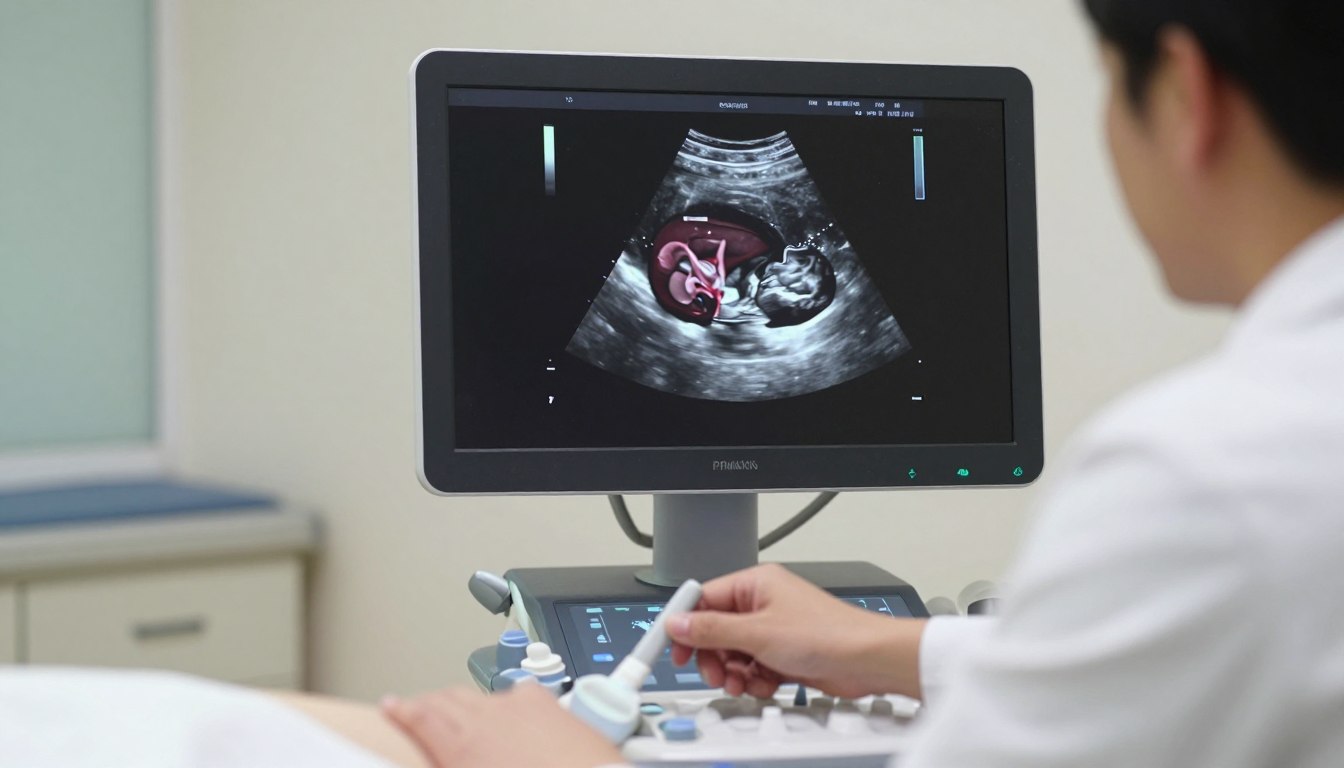

7 tydzień ciąży USG bicie serca – kiedy zwykle jest widoczne, normy tętna i co oznacza brak

Czy to możliwe, że pierwsze sygnały życia dziecka pojawią się szybciej niż myślisz? W 6–7 tygodniu badanie obrazowe często bywa pierwszą okazją, by zobaczyć czynność serca zarodka. To też zalecany…